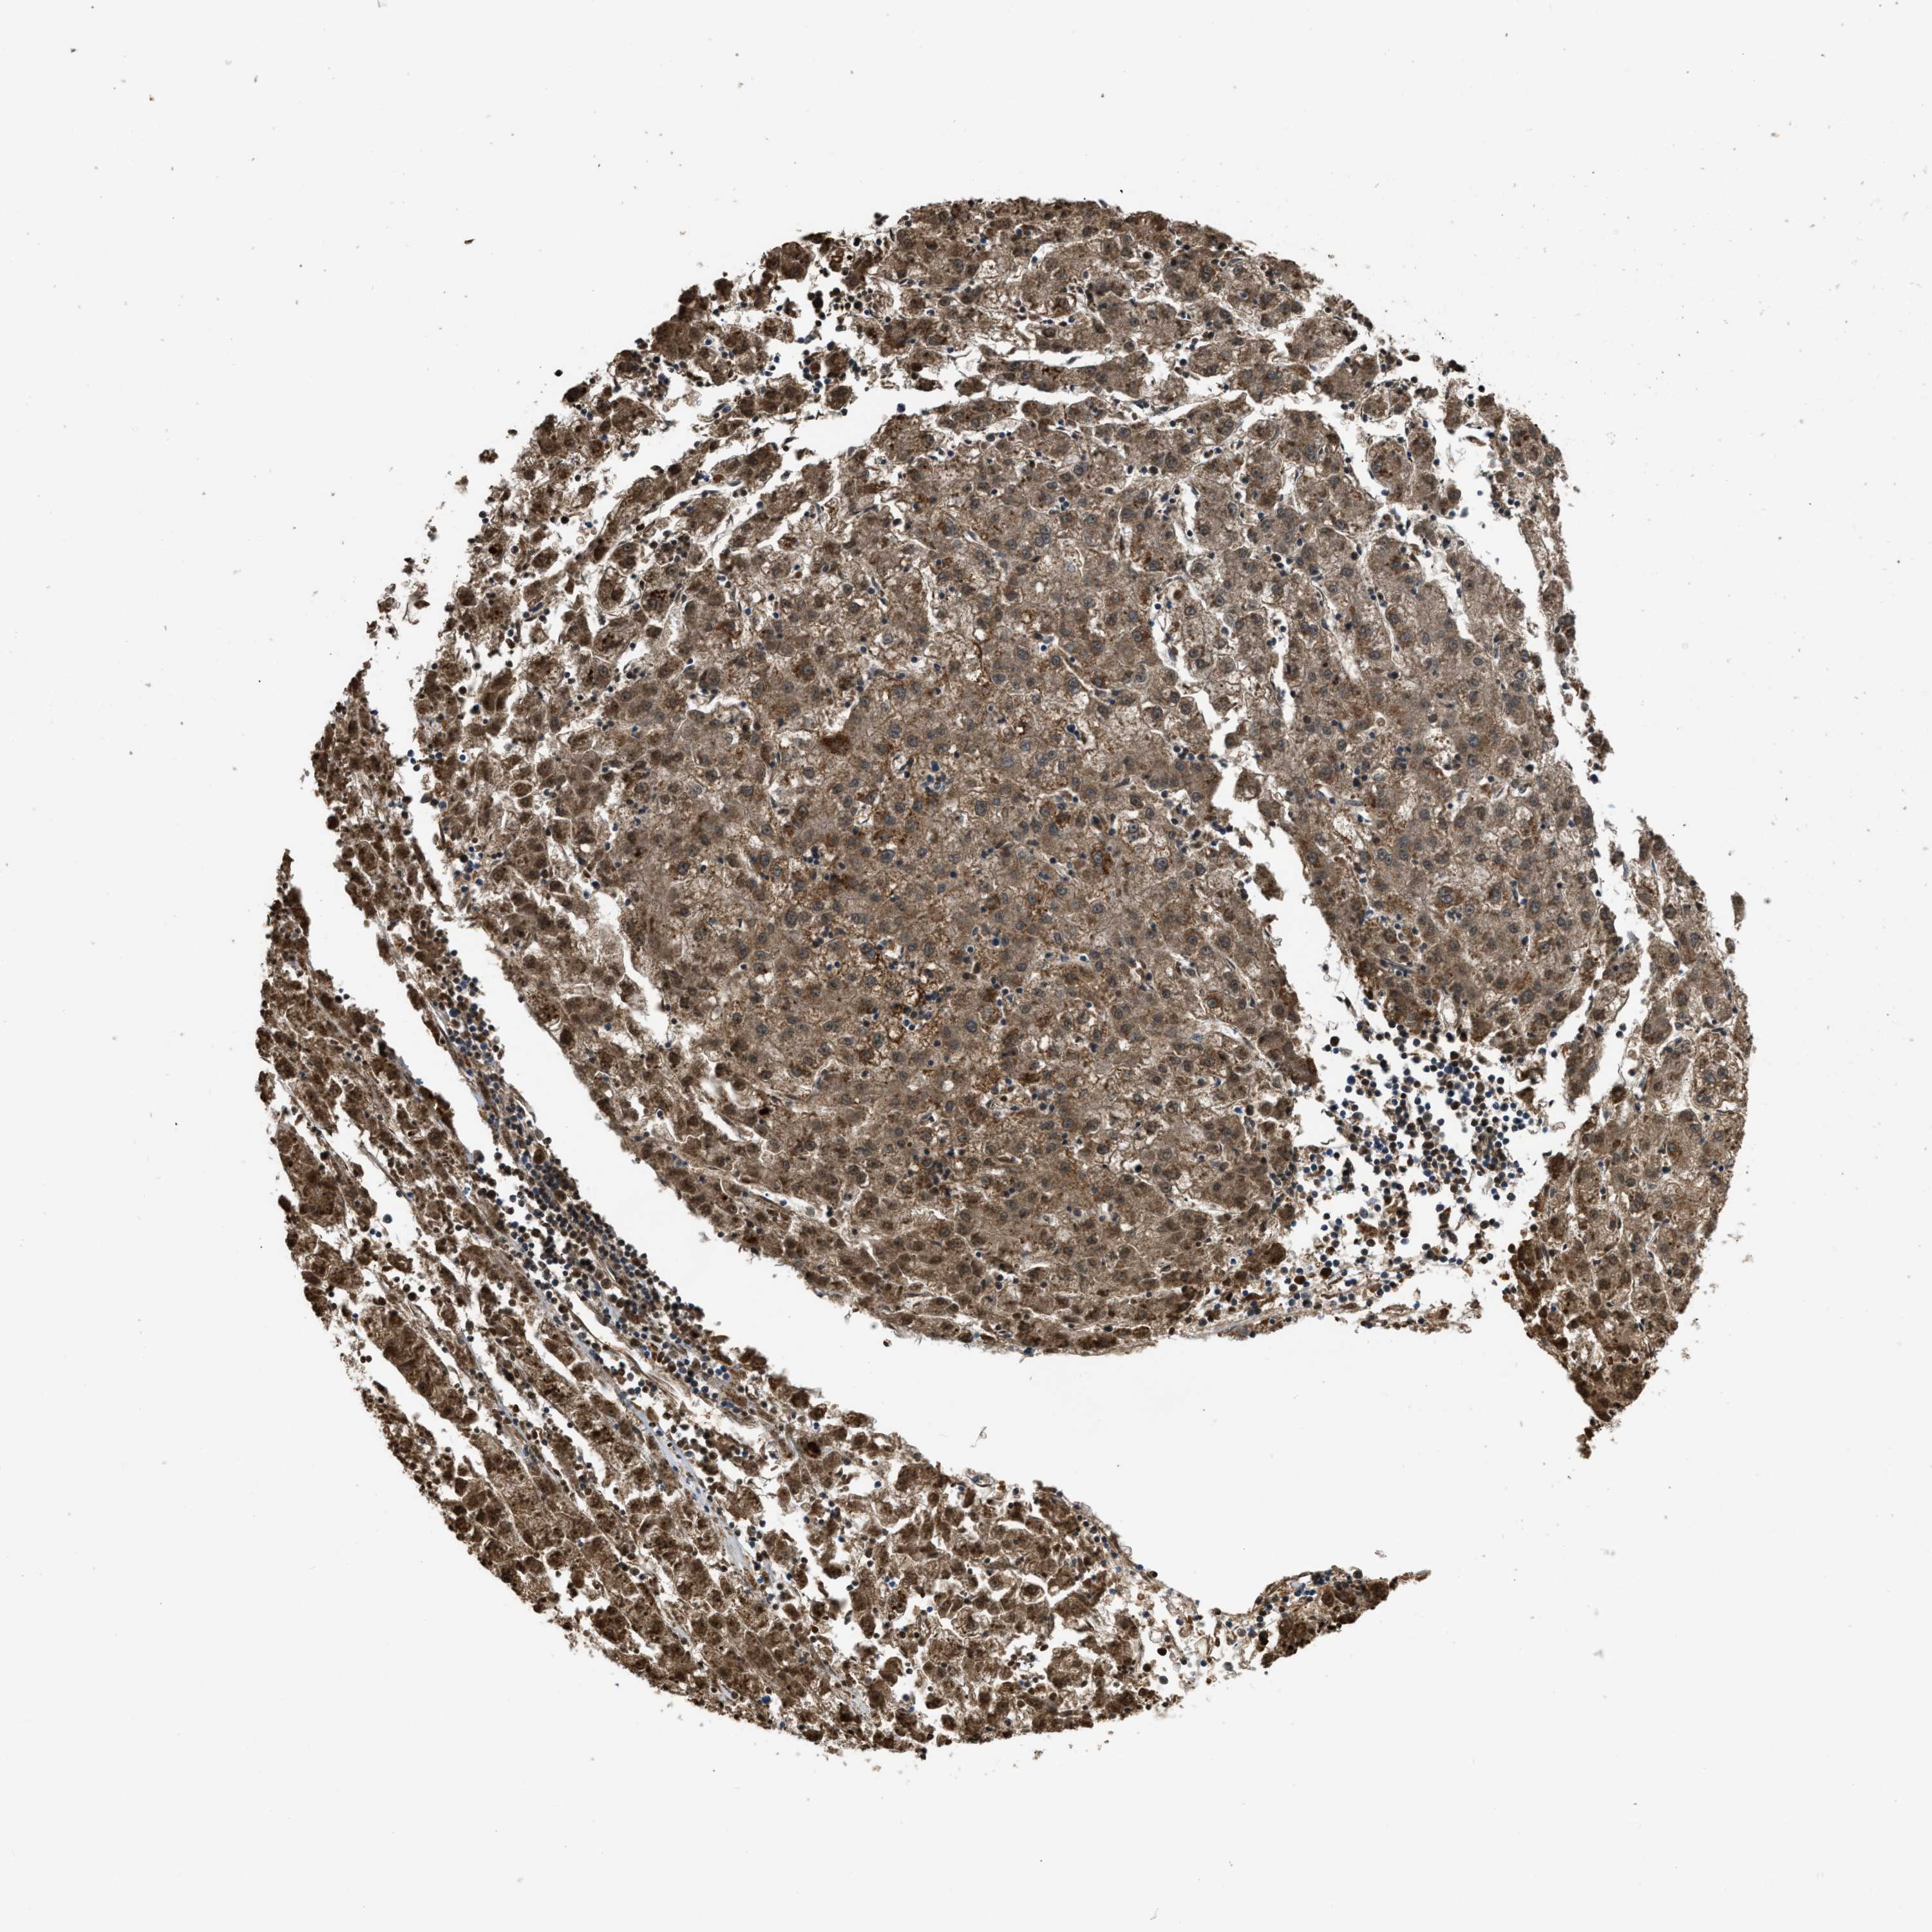

LIVER CANCER - Protein expressioni

A mouse-over function shows sample information and annotation data. Click on an image to view it in a full screen mode. Samples can be filtered based on level of antibody staining by selecting one or several of the following categories: high, medium, low and not detected. The assay and annotation is described here.

Note that samples used for immunohistochemistry by the Human Protein Atlas do not correspond to samples in the TCGA dataset.

Antibody stainingi

Antibody staining in the annotated cell types in the current human tissue is reported as not detected, low, medium, or high, based on conventional immunohistochemistry profiling in selected tissues. This score is based on the combination of the staining intensity and fraction of stained cells.

Each image is clickable and will lead to virtual microscopy that enables deeper exploration of all samples and also displays staining intensity scores, fraction scores and subcellular localization as well as patient and tissue information for each sample.

Antibody HPA018910

Antibody HPA018921

Antibody HPA018923

Staining

High

Medium

Low

Not detected

Intensity

Strong

Moderate

Weak

Negative

Quantity

>75%

75%-25%

<25%

None

Location

Nuclear

Cytoplasmic/membranous

Cytoplasmic/membranous,nuclear

Cholangiocarcinoma

Carcinoma, Hepatocellular, NOS